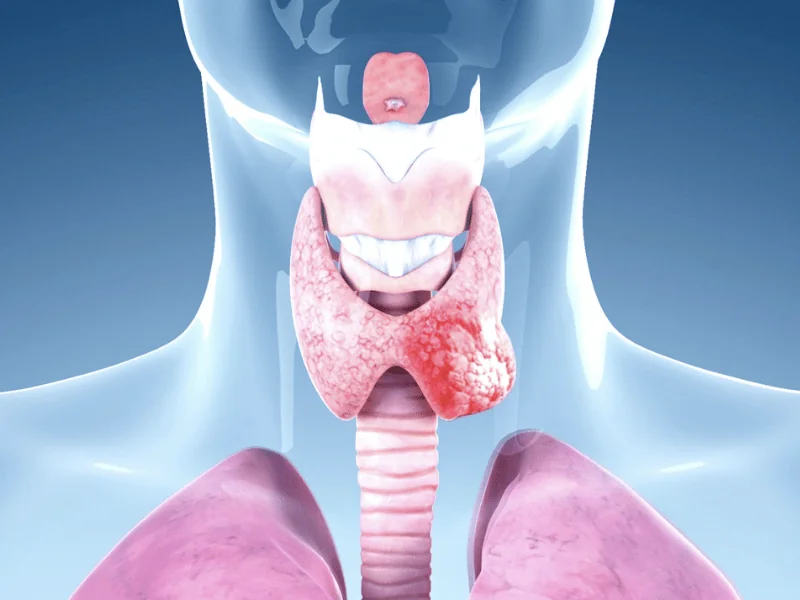

Tratamento do câncer de tireoide

O tratamento do câncer de tireoide envolve cirurgia, radioiodoterapia e terapia supressiva. O principal é a cirurgia, que pode ser parcial, total ou total com esvaziamento, e os outros tratamentos são adjuvantes. Quanto mais agressiva for a doença, mais agressivo será o tratamento. É por isso que alguns pacientes fazem apenas a tireoidectomia parcial e ficam curados, enquanto outros precisam ser operados várias vezes, fazer radioiodoterapia mais de uma vez. Cada caso é um caso.